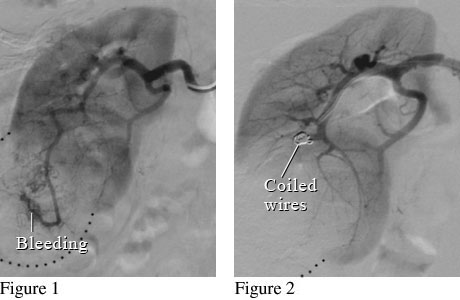

Angiogram of a Renal Mass

Figure 1 shows a kidney with a large mass that is bleeding. Figure 2 shows small coiled wires that have been placed in the artery to block the bleeding.